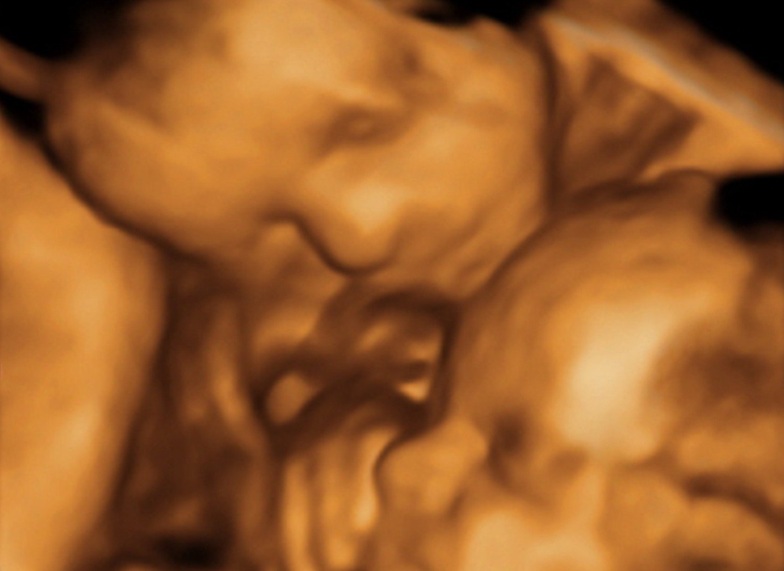

Последний триместр при многоплодной беременности - наиболее ответственное время. Известно, что двойни и тройни чаще всего появляются на свет раньше установленного срока. Поэтому крайне важно отслеживать состояние матери и плодов, чтобы при необходимости начать родоразрешение. Для этого используется ультразвуковое исследование с допплерометрией.

УЗИ обследование с параллельной допплерометрией проводился планово. Беременность с несколькими плодами сама по себе является показанием к непрестанному контролю за здоровьем плодов, особенно на поздних сроках. Крайне важно уточнить степень старения плаценты, измерить объем околоплодных вод и установить предлежание малышей. Отдельно рассматривается пуповина: нельзя, чтобы она была обвита вокруг шеи одного или нескольких детей. Также допплерометрия определяет, не страдает ли какой-то из плодов от гипоксии.

Что показывает УЗИ при многоплодной беременности в 3 триместре

При исследовании врач уделяет внимание конкретным показателям здоровья пациентки и каждого из плодов. Во время УЗИ оцениваются:

- размеры матки, длина и уровень раскрытия шейки;

- расположение пуповины;

- сердцебиение плодов;

- степень старения плаценты;

- любые патологии развития плодов;

- предлежание малышей.

Допплерометрия определяет, насколько нормально действуют кровоток и кислородный обмен. Также во время УЗИ удастся узнать пол плодов, если до этого исследование не проводилось.